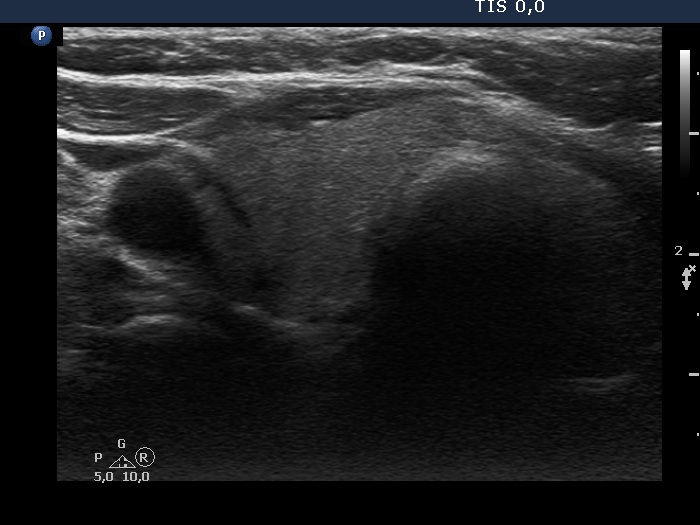

Ultrasonography. The thyroid was echonormal. There was a moderately hypoechoic nodule in the isthmus. The nodule had several intranodular hyperechogenic figures, probably back wall figures. The nodule did not show increase in size over the part two decades.